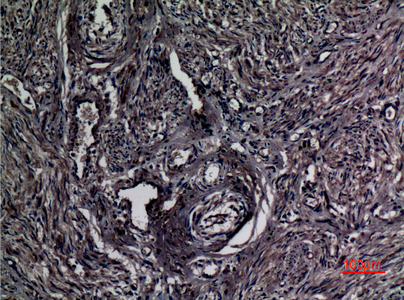

Immunohistochemistry analysis of paraffin-embedded Human ovary using A1BG antibody.High-pressure and temperature Sodium Citrate pH 6.0 was used for antigen retrieval.

Immunohistochemistry analysis of paraffin-embedded Human ovary using A1BG antibody. High-pressure and temperature Sodium Citrate pH 6.0 was used for antigen retrieval.